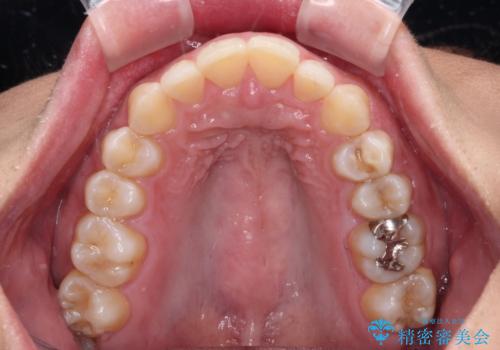

- 下顎前歯部には叢生が認められ、口を自然に閉じにくい状態でした。また、噛み合わせが深い「ディープバイト」の状態で、見た目だけでなく将来的な奥歯への負担も懸念されました。

口元の突出感を改善するため、上下左右の小臼歯4本を抜歯する矯正治療を計画しました。

「矯正装置が目立つのは避けたい」というご希望があったため、プラスチックブラケット+コーティングワイヤーを使用した審美装置を選択しました。